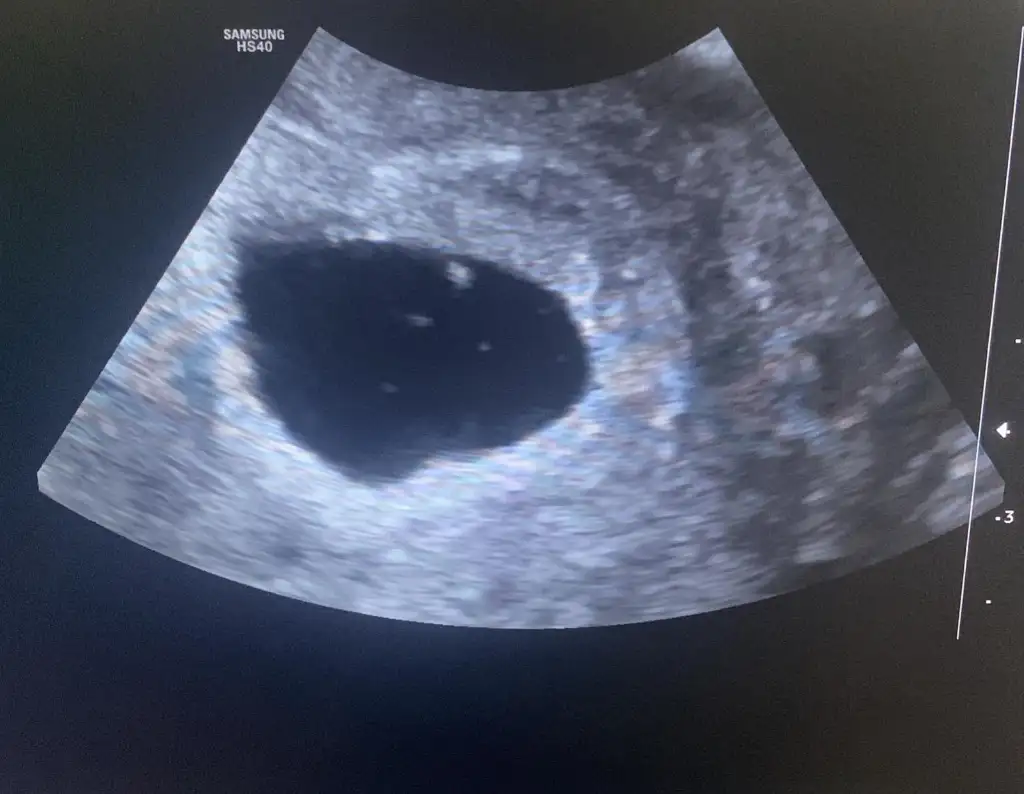

Ultrasonda 5+4 görunuyo bebeği görduk 2 mm ama daha kalp atışı yok normal mi sizce ben cok korkuyorum

Evet şukur görundu bebeğide görduk cok kucuk daha 2 mm doktor bebeğin kalbini duymamız icin en az 4 mm olması lazım dediÇok norevet gorundu mal endişelenmeyin yolk sac gözüktü mü fotosu var mı

Ben de 5+2 deyim perşembe günü gideceğim zor ama inşallah görürüm kalp atışınıEvet şukur görundu bebeğide görduk cok kucuk daha 2 mm doktor bebeğin kalbini duymamız icin en az 4 mm olması lazım dedi

Ben de dün doktora gittim. 5+5de. Kalp atışını haftaya duyarız dedi doktor. Kese 13mmBen de 5+2 deyim perşembe günü gideceğim zor ama inşallah görürüm kalp atışını